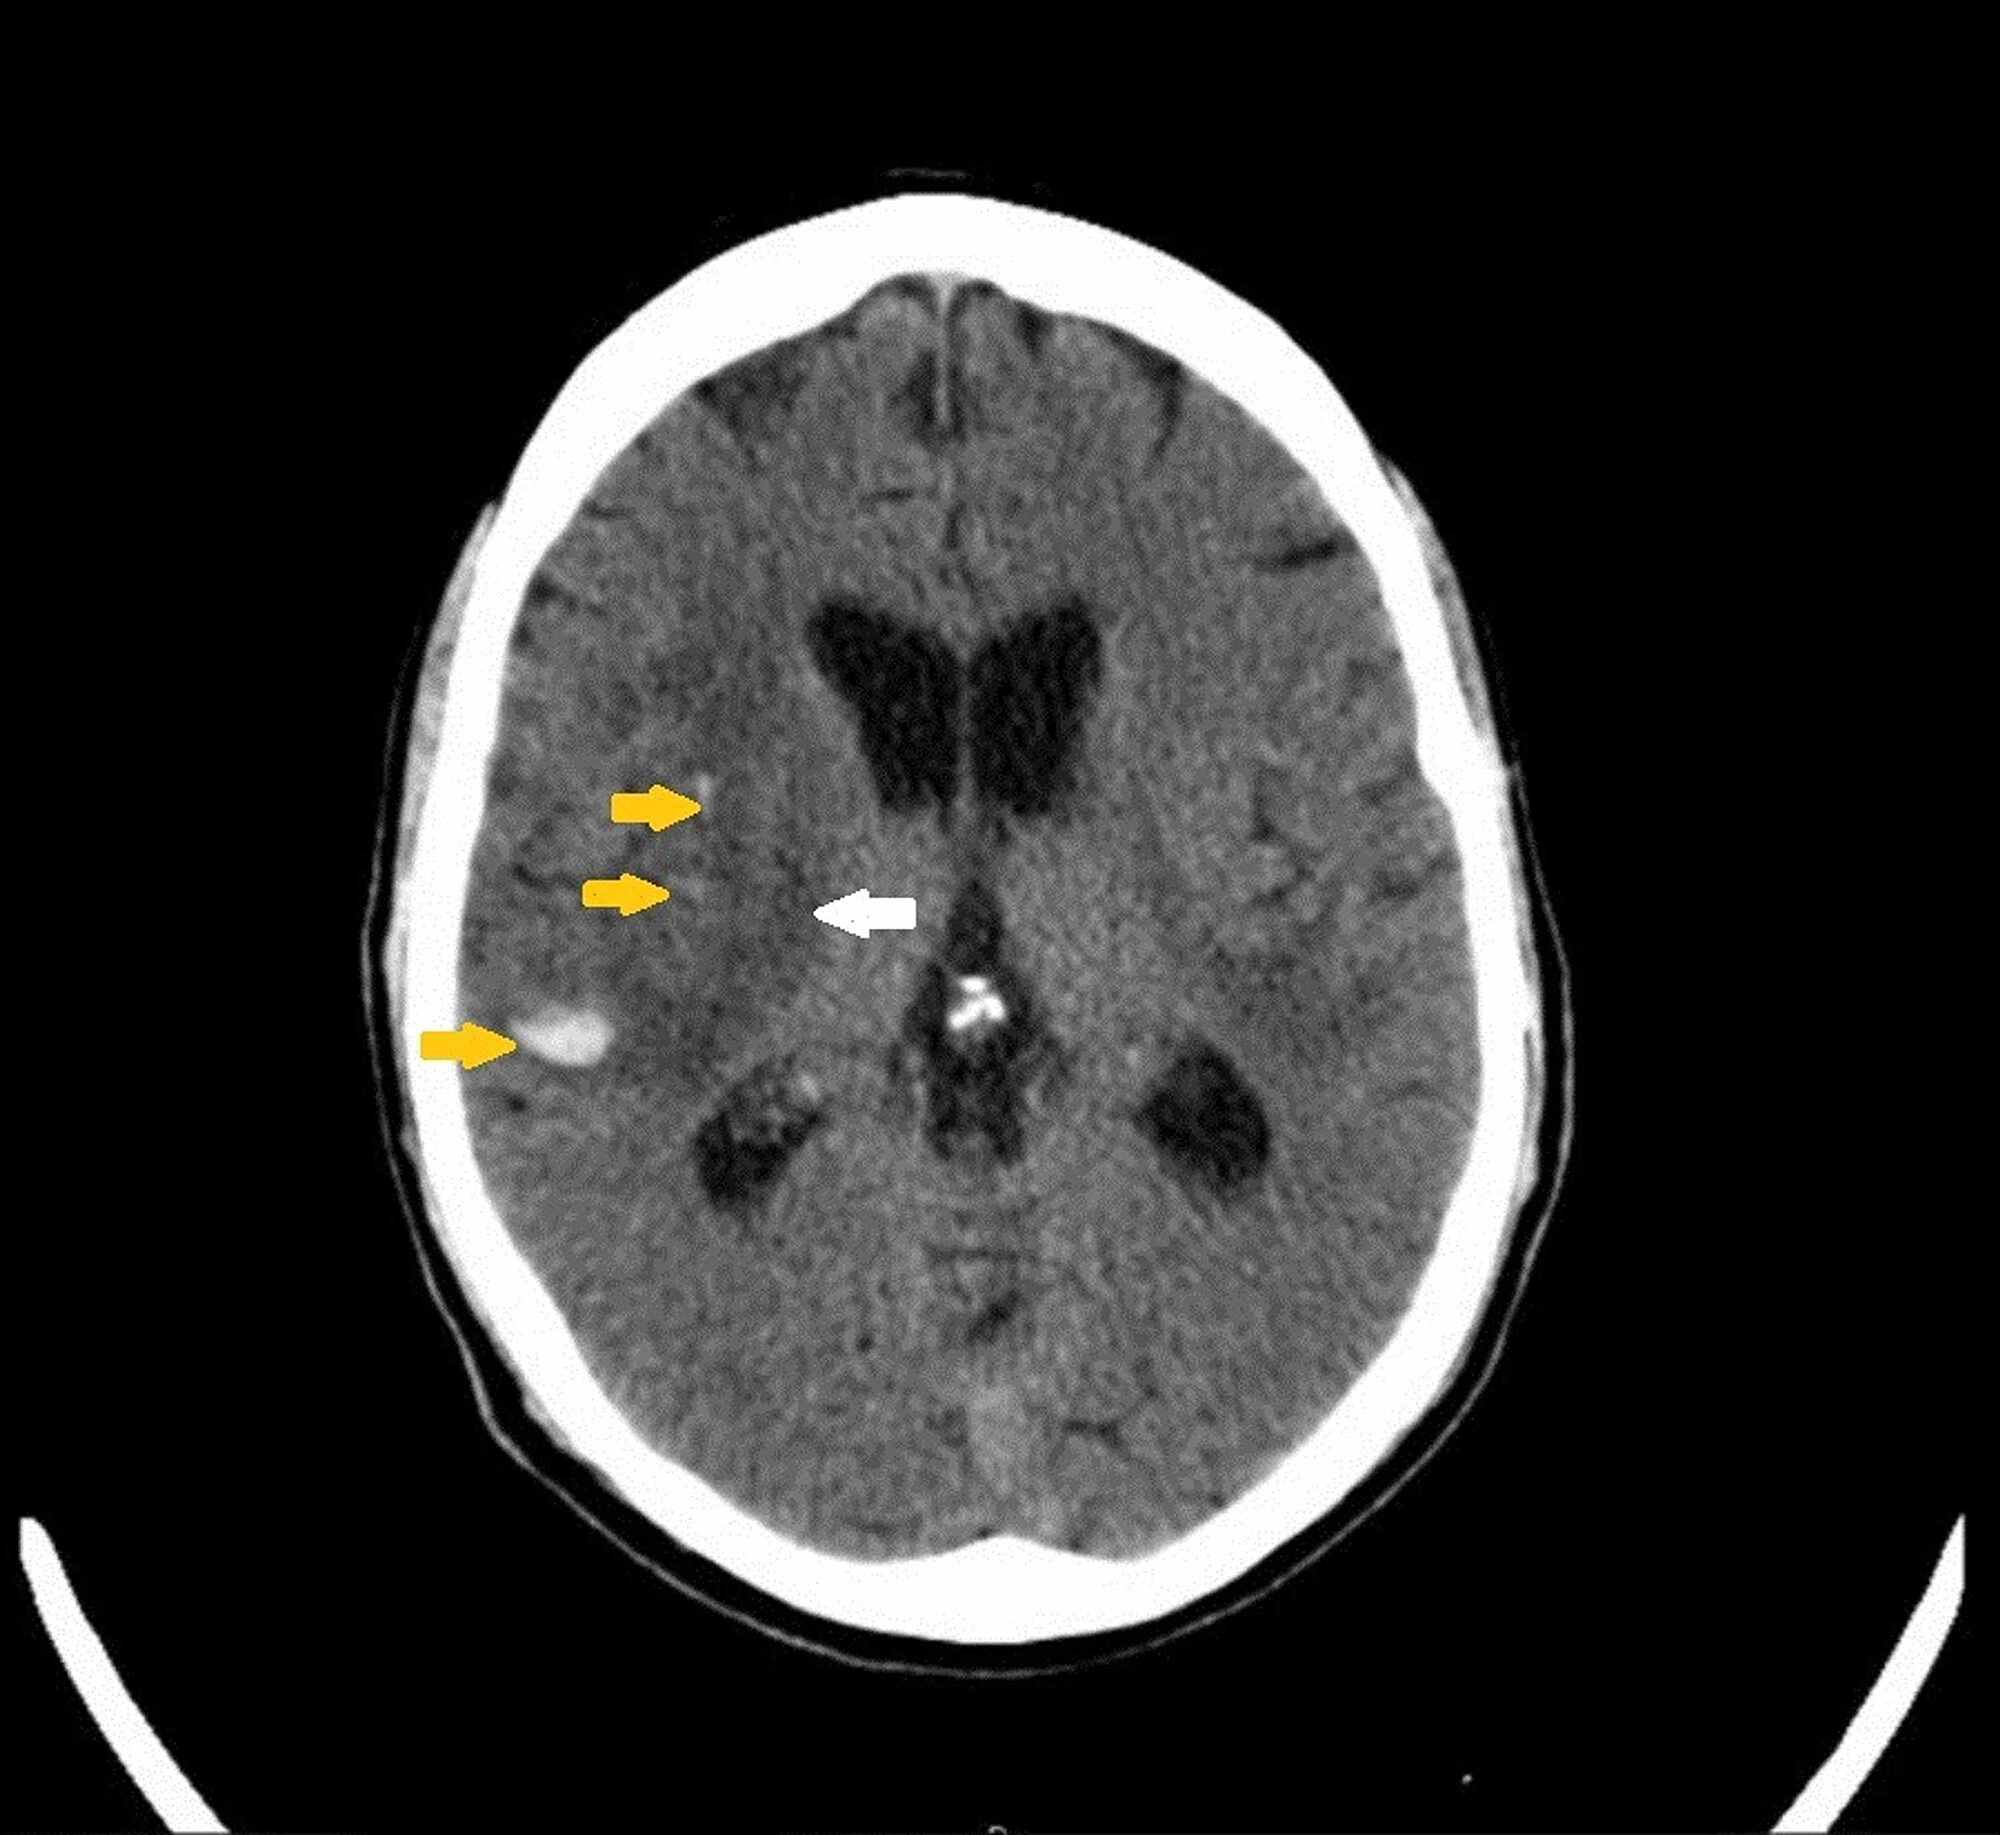

CT scans demonstrating a thick clot remaining around perimesencephalic Are Ct Scans Overused an obvious limitation of ct is ionizing radiation; Computed tomography (ct) is frequently used in the emergency department (ed) to make diagnoses and guide management decisions. They’re linked to higher rates of cancer—and they’re medically unnecessary in up to 50 percent of cases—but health experts are having a hard time curbing. In addition there are economic implications to overuse.. Are Ct Scans Overused.